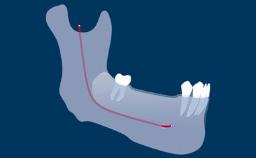

- describe how implant positioning can lead to esthetic complications